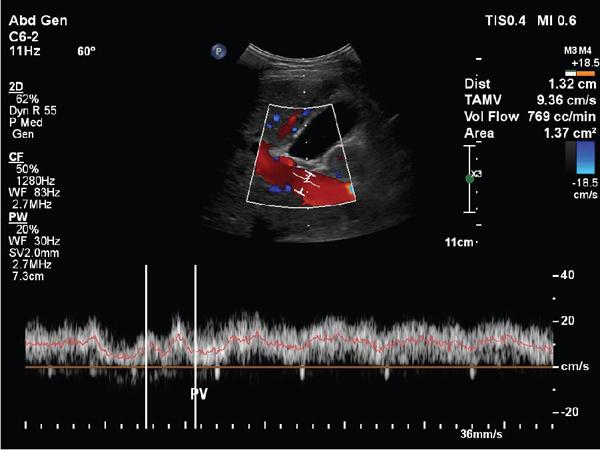

Shrinivas B. Desai, Ritu K. Kashikar, Aman Snehil, Ajay Jhaveri Cirrhosis is a late stage of irreversible scarring of the liver causing abnormality in liver structure and function. Multiple conditions and factors can cause repeated liver damage and scarring ultimately leading to cirrhosis. The most feared complication of liver cirrhosis is the development of hepatocellular carcinoma (HCC). Portal hypertension (PHT) is seen with a variety of conditions but cirrhosis happens to the most important cause. Imaging plays a vital role in noninvasive diagnosis and treatment planning of both cirrhosis and PHT. Liver imaging reporting and data system (LI-RADS) is a standardized reporting system assigning an observation risk of representing HCC. This chapter focuses on discussing aetiologies and imaging of PHT with a lucid review of L1-RADS 2018 version. The portal blood circulation is a unique circulatory circuit as it connects two capillary beds between the liver parenchyma at one end and the gastrointestinal tract and splenic parenchyma at the other end. The portal system ramifies in the liver and ultimately ends in the hepatic sinusoids from where the blood ultimately drains into the inferior vena cava (IVC). The portal vein (PV) originates from the capillary beds in the stomach, intestine and the spleen. The main PV is formed behind the neck of the pancreas by the confluence of the superior mesenteric vein (SMV) and splenic vein. It continues to the porta hepatis where it bifurcates into the left and right branches as it carries nutrient rich but oxygen poor blood to the liver (Fig. 9.9.1). The PV makes up for 75%–80% of the liver’s blood supply while the hepatic artery which arises from the celiac trunk makes up for the remaining 25%. A pathological increase in the portal venous pressure is referred to as PHT. PHT is most often a sequel of chronic parenchymal liver disease and leads to major life-threatening complications due to bleeding from the collateral circulation (most commonly oesophageal varices). Direct measurement of portal pressure (PP) is invasive and often not feasible in most patients and thus imaging plays an important role in the diagnosis of PHT and its complications. The normal portal venous pressure ranges between 5 and 10 mmHg, which is the equivalent of 7–14 cm H2O. The normal hepatic venous pressure gradient (HVPG) is the pressure gradient between the PV and the IVC, is typically 1–5 mmHg. Presence of PHT is indicated by a wedged hepatic venous pressure of more than 5 mmHg. Other definitions include a splenic pressure of more than 15 mmHg or an intraoperative PP of greater than 30 cm H2O. The complications of PHT are seen when HVPG is greater than 10 mmHg and hence this value defines clinically significant PHT. Variceal bleeding is seen with a pressure greater than 12 mmHg. In ideal conditions, the portal circuit is a high flow, low resistance circuit as it has to allow substantial flow rates of 700–1000 mL/min to the hepatic parenchyma from the gastrointestinal tract. Anatomical changes in the organization of the hepatic lobule can result in rise in the portal resistance. These can occur in the form of collagen deposition in the space of Disse, fibrotic scars formed due to regenerative nodule (RN) formation, loss of normal elasticity of the endothelium and distal venous thrombosis. Changes in splanchnic haemodynamics due to factors that increase splanchnic blood flow and increase in intrahepatic vascular resistance due to transformation of stellate cells into myofibroblasts also contribute to the increase in PP gradient. In Western countries, alcoholic cirrhosis and viral cirrhosis are the leading causes of PHT and oesophageal varices. The viral causes form majority of cases leading to cirrhosis and PHT in the Far East and Middle Eastern countries while Schistosomiasis remains an important cause in the African countries. Worldwide, nonalcoholic steatohepatitis (NASH) and hepatitis C are the emerging causes of chronic liver disease (CLD) and PHT. PHT can be classified as cirrhotic and noncirrhotic depending on whether it is associated with cirrhosis or not. This distinction is important as noncirrhotic causes like PV thrombosis are at high risk of development of bleeding but tend to have a better chance of surviving a variceal bleed than a patient with decompensated alcoholic cirrhosis due to preserved hepatic synthetic functions in the former. PHT can also be classified on the basis of the location of the pathology into prehepatic, hepatic and posthepatic causes. Hepatic causes can further be divided into presinusoidal, sinusoidal and postsinusoidal. The causes of portal hypertension have been denoted in Table 9.9.1. The direct measurement of the PP by measuring the HVPG is invasive, expensive not readily available in all patients. Thus, imaging plays an important role in the diagnosis of PHT. Various modalities are used for the imaging diagnosis of PHT. Ultrasonography (USG) and Doppler evaluation have the advantage of being inexpensive, readily available and bedside modality (Table 9.9.2). The role of ultrasound and Doppler in imaging of PHT is to: Grey scale imaging is useful in evaluating the splenoportal anatomy. The evaluation should begin with the liver morphology. Signs of cirrhosis like nodularity of the liver surface with relative atrophy of the right lobe and prominence of the left lobe and caudate should be looked for. Hepatic echotexture appears coarse and more echogenic (Table 9.9.3). Increase in portal venous diameter is a sign of PHT (Fig. 9.9.2). Portal venous diameter of more than 13 or 15 mm has low sensitivity for diagnosing PHT of only 40%–12.5%, respectively. Absolute measurement of the portal diameter as a sign of PHT is also fallacious as in presence of collateral circulation or hepatofugal flow; there may actually be a decrease in the PV diameter. Therefore, a more accurate sign is respiratory variation of PV diameter. An increase in PV diameter of less than 20% with deep inspiration has been reported to indicate PHT with a sensitivity of 80% and specificity of 100%. This has been reported to be an accurate indicator of cirrhosis. Hepatic vein straightness, uniformity of vein wall echogenicity and visualization of at least 1 cm segment of the hepatic vein are the parameters used for evaluation. Splenomegaly is defined as bipolar splenic diameter of greater than 12 cm or largest splenic cross-sectional area passing through the hilum of greater than 45 cm2, and occurs secondary to PHT (Fig. 9.9.3). A total of 65%–80% patients with cirrhosis have splenomegaly on ultrasound. Patients with cirrhosis due to viral hepatitis and primary biliary cirrhosis show splenomegaly more frequently than those with alcoholic cirrhosis. This is an accurate sign of PHT. USG is extremely sensitive with respect to detecting subclinical ascites. Perihepatic space is the most usual site of visualization of minimal ascites. In normal subjects, this ratio is approximately 0.07 and a value above 0.1 suggests the diagnosis of PHT with a 95% sensitivity and specificity. The normal spectral waveform of the hepatic artery is a low resistance flow pattern with forward flow in diastole and a resistivity index in the range of 0.5–0.7. In PHT, the resistivity index of the hepatic artery increases with high resistance flow pattern due to increased peripheral vascular resistance. Resistance index (RI) > 0.78 in the intrahepatic branches of the hepatic artery has been reported to have a sensitivity of 50% and a specificity of 100% for the detection of PHT (Fig. 9.9.11). Pulsatility index (PI) > 1.05 suggests severe PHT with a sensitivity of 86% and specificity of 88% (Fig. 9.9.11). Patency of hepatic veins should be evaluated to rule out Budd–Chiari syndrome as a cause of PHT. The normal hepatic venous waveform (HVW) reflects right atrial activity and this results in a triphasic waveform with one positive and two negative waves. In PHT, this waveform becomes monophasic or biphasic. A monophasic HVW has a sensitivity and specificity of 74% and 95%, respectively, in the diagnosis of severe PHT (Fig. 9.9.12). Dilatation of the splanchnic veins – the SMV and the splenic vein – more than 11 mm are suggestive of PHT with a sensitivity and specificity of 72% and 100%, respectively. A reduction in the respiratory variation of the splenic vein and SMV to less than 40% had a sensitivity and specificity of 79.7% and 100%, respectively, for the diagnosis of PHT (Fig. 9.9.13). The splenic artery reveals an increase in the resistivity index and an RI of >0.63 and a PI of >1 have a sensitivity and specificity of 84.6% and 70.4% for the diagnosis of PHT. Presence of portosystemic collaterals like patent paraumbilical vein, dilated left gastric and short gastric veins are 100% specific sign for PHT (Figs. 9.9.14–9.9.16). Recanalization of the paraumbilical vein, known as the Cruveilhier–Baumgarten syndrome is observed in 43% of patients with PHT, and this is the easiest collateral to assess during the US examination. Various portosystemic collaterals that occur in PHT have been discussed in details in subsection on CT findings in PHT. No Doppler parameter is considered reliable enough to measure PP with sufficient accuracy for use in clinical practice. Oesophageal varices are often present in patients with portosystemic collaterals. Appearance or increase in number of collaterals along with splenomegaly has a high association with variceal formation and growth. USG helps in diagnosis of prehepatic causes like portal stenosis or thrombosis by demonstrating the patency and morphology of the splenoportal system. Arteriovenous fistulae and tumours causing vascular thrombosis as aetiology can be readily detected. USG helps in diagnosis of features of cirrhosis and thus helps differentiate noncirrhotic causes of PHT. USG allows diagnosis of fatty liver disease, which is an emerging cause of cirrhosis. Among the posthepatic causes, USG aids in establishing the diagnosis of Budd–Chiari syndrome by demonstrating the patency and morphology of the IVC and hepatic veins. Owing to the inability of CT to detect flow direction, portal flow rates or pressure gradients, CT is not the primary modality in diagnosis of PHT. Similar to USG dilatation of portosystemic system is a feature of PHT (Fig. 9.9.17). Changes in cirrhosis if present can be seen in the form of surface nodularity, nodules and fibrous septae. CT plays an important role in diagnosis of portal venous thrombosis and evaluating its extent. An acute thrombus is seen as a hypodense filling defect in the vessel causing distension of the venous lumen. Surrounding fat stranding can be seen. A chronic thrombus appears as an eccentric filling defect usually along the wall and is often associated with decrease in vessel diameter. Calcification may be seen in chronic thrombi. Multidetector computed tomography (MDCT) is a useful tool to evaluate portosystemic collateral circulation and recognize complications of PHT. 3D angiography can help understand portal venous and complex variceal anatomy and plan treatment. The various portosystemic collaterals are discussed below. They can be classified into those draining into superior vena cava (SVC) and those draining into the IVC. Magnetic resonance imaging (MRI) is a noninvasive modality used in the evaluation of PHT without the use of ionising radiation. It provides evaluation of parenchymal abnormalities, collaterals and characterization of tumours (Fig. 9.9.28). Spin echo sequences allow characterization of liver masses and liver parenchyma. Loss of flow void allows for detection of thrombosis. Time-of-flight (TOF) angiography is useful in assessing the portal venous system and allows for successful detection of PV thrombosis. The disadvantages of TOF are motion artefacts caused by breathing, long acquisition times and incomplete coverage of the portal venous system. Novel imaging techniques include phase contrast, T1 mapping and magnetic resonance elastography (MRE). The advantage of phase contrast over TOF imaging is that phase contrast imaging acquires information regarding the flow direction in addition to the information regarding the flow velocity. On-phase contrast images signal within vessel is hyperintense when flow is cranial and hypointense when flow is caudal. Look-Locker imaging technique using gradient echo (GRE) MRI sequences with inversion recovery pulse is used to quantify fibrosis by measuring precontrast T1 relaxation times. Interventions in PHT can be aimed at diagnosis or more commonly at management of complications of PHT. HVPG measurement, which is the gold standard for the diagnosis of PHT, can be achieved through cannulation of the PV. Transjugular hepatic biopsy is another diagnostic invasive technique that also allows indirect measurement of PP. Disadvantages include deterioration of hepatic function caused by diversion of portal venous blood flow and shunt dysfunction. TIPSS is contraindicated in patients with congestive heart failure, severe pulmonary hypertension, severe tricuspid regurgitation and hepatic failure. In this technique, a catheter is advanced from the femoral vein into the outlet of the gastrorenal, usually in the region of the left renal vein. The shunt is then occluded with a balloon and sclerosant is injected retrograde to occlude the gastric varices. Histological development of RNs surrounded by fibrous septae in response to chronic liver injury, progressing PHT and end-stage liver disease is termed as cirrhosis. Although initially considered an end-stage phenomenon in CLD, recent evidence suggests that the histological fibrosis can be reversible in early stages with the initiation of specific therapies, for example, in viral cirrhosis with the initiation of antiviral therapy. The one-year mortality rate in cirrhosis varies widely from 1% to 57% depending on the occurrence of complications. Cirrhosis can have a wide variety of causes ranging from congenital to acquired and infectious to noninfectious. It is also a major aetiologic risk factor for the development of HCC. Imaging plays an important role in aetiologic diagnosis of this diverse entity as well as in the diagnosis and management of its complication and surveillance for oncological transformation.

Doppler assessment of portal hypertension (Table 9.9.4)

A. Portal vein